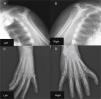

The patient also underwent X-ray of the shoulder girdle and upper arm, which showed hypoplasia of the glenoid cavity and bilateral degenerative changes of the gleno-humeral joints; bilateral X-ray of the elbow, fist and hand showed right elbow luxation in the radio-humeral joint, with normal morphology of the left elbow, morphological changes to the proximal carpal row of the right fist, the first finger of the right hand morphologically similar to the others, and syndactyly between the first and second axes of the left hand and wrist; the trapezium and trapezoid could not be differentiated (Figure 4).

Shoulder girdle X-ray showing hypoplasia of the glenoid cavity and bilateral degenerative changes of the gleno-humeral joints (A and B); X-ray showing syndactyly between the first and second axes of the left hand and wrist; the trapezium and trapezoid cannot be differentiated (C); right hand with morphological changes of the proximal carpal row; the first finger of the right hand is morphologically similar to the others (D).

In the present case the patient had evident abnormalities of both upper limbs since birth that were subsequently confirmed by typical radiographic findings, with hypoplasia of the glenoid cavity, bilateral degenerative changes of the gleno-humeral joints, morphological changes to the proximal carpal row of the right hand, the first finger of the right hand morphologically similar to the others, and syndactyly between the 1st and 2nd axes of the left hand and wrist; the trapezium and trapezoid could not be differentiated.